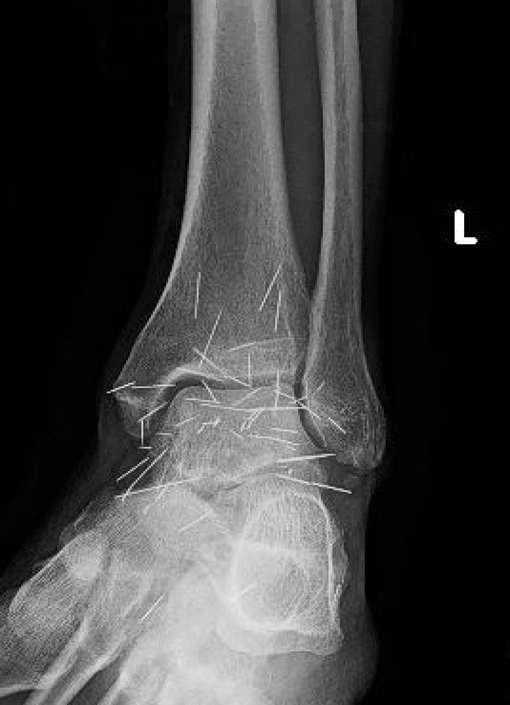

On physical exam, one could note small scars and palpable foreign bodies along the anterior, lateral, and medial aspects of the ankle joint with decreased range of motion and decreased sensation along lateral leg and foot. Of note, Tinel’s and Valleix’s signs were negative at the ankle, which we feel was likely secondary to neuropraxia at a more proximal level.

X-ray imaging revealed numerous needle-like metallic foreign bodies. We prescribed gabapentin and ordered electromyography/nerve conduction velocity (EMG/NCV) studies. These studies revealed evidence of left peroneal neuropathy, most commonly seen at the fibular head. The study also noted increased duration, increased amplitude, and decreased recruitment in the left posterior tibial, peroneus longus and extensor hallucis longus muscles. The patient found little relief with conservative measures.